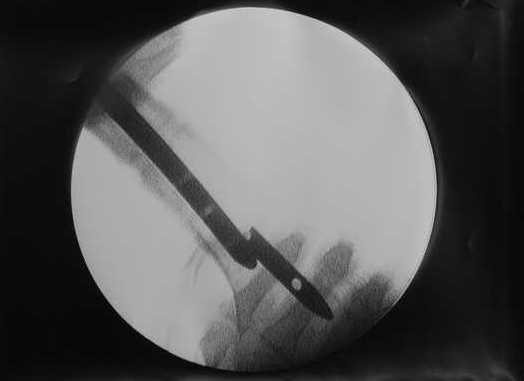

27 марта выполнено удаление блокирующих винтов (сломанный винт пришлось высверливать цапфен-бором), сломанного штифта (дистальный фрагмент удален через канал, образованный разверткой из коленного сустава - image 4),

рассверливание костно-мозгового канала, реостеосинтез штифтом UFN (при проведении штифта в дистальном отломке мы использовали поляризующий винт, диаметр штифта 10 мм). После операции в связи гемартрозом дважды (на 1 и 3 сутки) выполняли пункцию коленного сустава. Сейчас признаков скопления жидкости в полости сустава нет. Послеоперационные рентгенограммы - images 5, 6, 7.